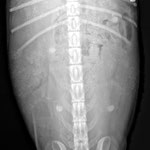

Hündinnen tragen normalerweise 63 Tage. Da man aber (ohne aufwändige medizinische Tests) den genauen Zeitpunkt des Eisprungs nur nach dem Datum der Deckungsbereitschaft der Hündin abschätzen kann, bleibt auch der voraussichtliche Wurftermin nur eine Schätzung. Erst ab dem 25. Trächtigkeitstag kann man mittels Ultraschall feststellen, ob die Hündin überhaupt trägt. Ihr äusserlich ansehen kann man das sogar erst ab ungefähr dem 40. Tag. Es könnte ja aber auch immer noch eine Scheinträchtigkeit sein. Gewissheit gibt ein Röntgen, das ab dem 45. Tag gefahrlos gemacht werden kann.